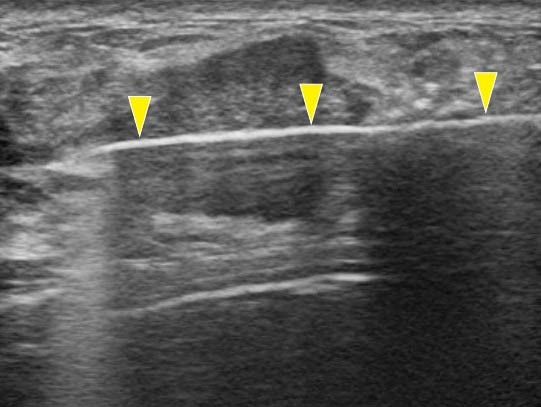

VAB超音波写真

乳腺診療には超音波検査が重要です。しこり、痛みなど乳腺の異常がある場合には診察と乳腺超音波検査を行い、実際にしこり(腫瘍など)があるかどうかを判断します。当クリニックでは富士フイルムヘルスケア社の超音波診断装置を使用しており、高周波プローブによって乳腺の繊細な画像検査が可能です。またリアルタイムエラストグラフィという機能でしこりの硬さを推定することができ、より正確な診断に役立ちます。

超音波検査で観察したしこりが乳がんを疑わず、良性疾患の可能性が高い場合には定期的な超音波検査による経過観察を行います。一方、しこりに悪性の可能性がある場合にはまず穿刺吸引細胞診(FNA:fine needle aspiration)を行います。これは注射に用いる針よりも細い針で乳腺のしこりなどから細胞を吸引し、顕微鏡で診断する検査です。この結果、悪性と判断されれば更なる精密検査を行い、乳がんに対する治療計画を立てていきます。FNAでも良悪性の判定が困難な場合や早期の乳がんが疑われ、ある一定量の組織採取が必要な場合には乳腺針生検を行います。当院ではより正確な診断をおこなうために、吸引をかけて組織を確保しながら針生検を行うVAB(vacuum-assisted breast biopsy)を行っています。FNAもVABも超音波検査で針の方向を確認しながら行います。